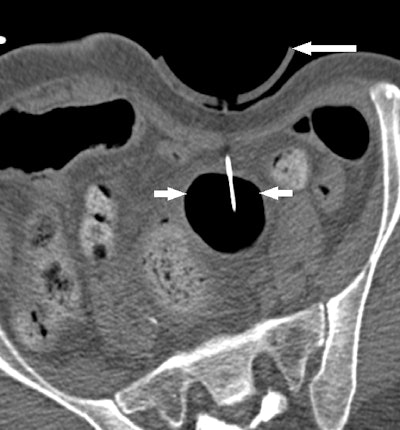

At Brigham, radiologists some time ago modified F-Spoon by cutting a keyhole-shaped notch in the spoon that made it better for guiding needle interventions during CT fluoroscopy studies. By inserting a needle into the keyhole notch, radiologists could compress the abdomen to move bowel loops aside while inserting needles, and they could also keep their hands out of the x-ray beam.

Ultimately, 15 procedures were deemed "questionably feasible" but difficult to perform without the paddle, four were rated as "not feasible" without the device, and two were categorized as feasible without the device but facilitated by the use of it. A particular benefit was the ability to use the paddle to steer the needle by applying pressure against it from inside the keyhole.

Because the goal of the original F-Spoon was to help radiologists avoid radiation while guiding interventional procedures, the Brigham group also measured the amount of radiation dose at the site of the skin incision point for the two abscess drainages, calculating a mean radiation dose of 14.95 mGy. For point of reference, the group calculated a mean radiation dose of 0.31 mGy to the operator's finger, just 2% of the mean dose recorded at the incision point.